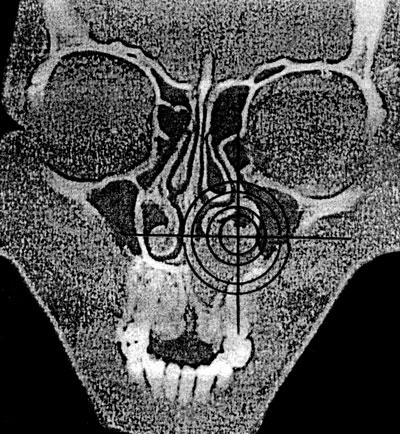

Оценка положения органа или его части может производиться как качественно, так и количественно (глубина залегания органа по кратчайшему расстоянию от поверхности, расчет координат с использованием осей абсцисс и ординат) – рис. 8.

Рис. 8. Определение координат кисты центрального отдела верхней челюсти (срез на уровне премоляров) на компьютерной томограмме (по: Соловьев М. М., Семенов Г. М., Галецкий Д. В., 2004).

Для реализации количественного подхода необходим выбор ориентации плоскости условного сечения и определение точки отсчета. К наиболее простым способам относится определение координат в горизонтальной плоскости с расположением «нулевой» точки в центре тела позвонка. Последовательное изменение угла обзора, а также компьютерное интегрирование (наложение) полученных изображений позволяет составить целостное представление об особенностях топографии анализируемого объекта.